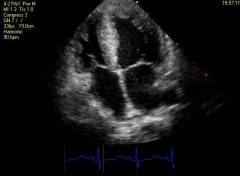

| Поражение сердечнососудистой системы |

| Поражение коронарных (венечных) артерий, отходящих от аорты и несущих кровь к сердечной мышце. |

| Поражение сердца (редкое проявление) |